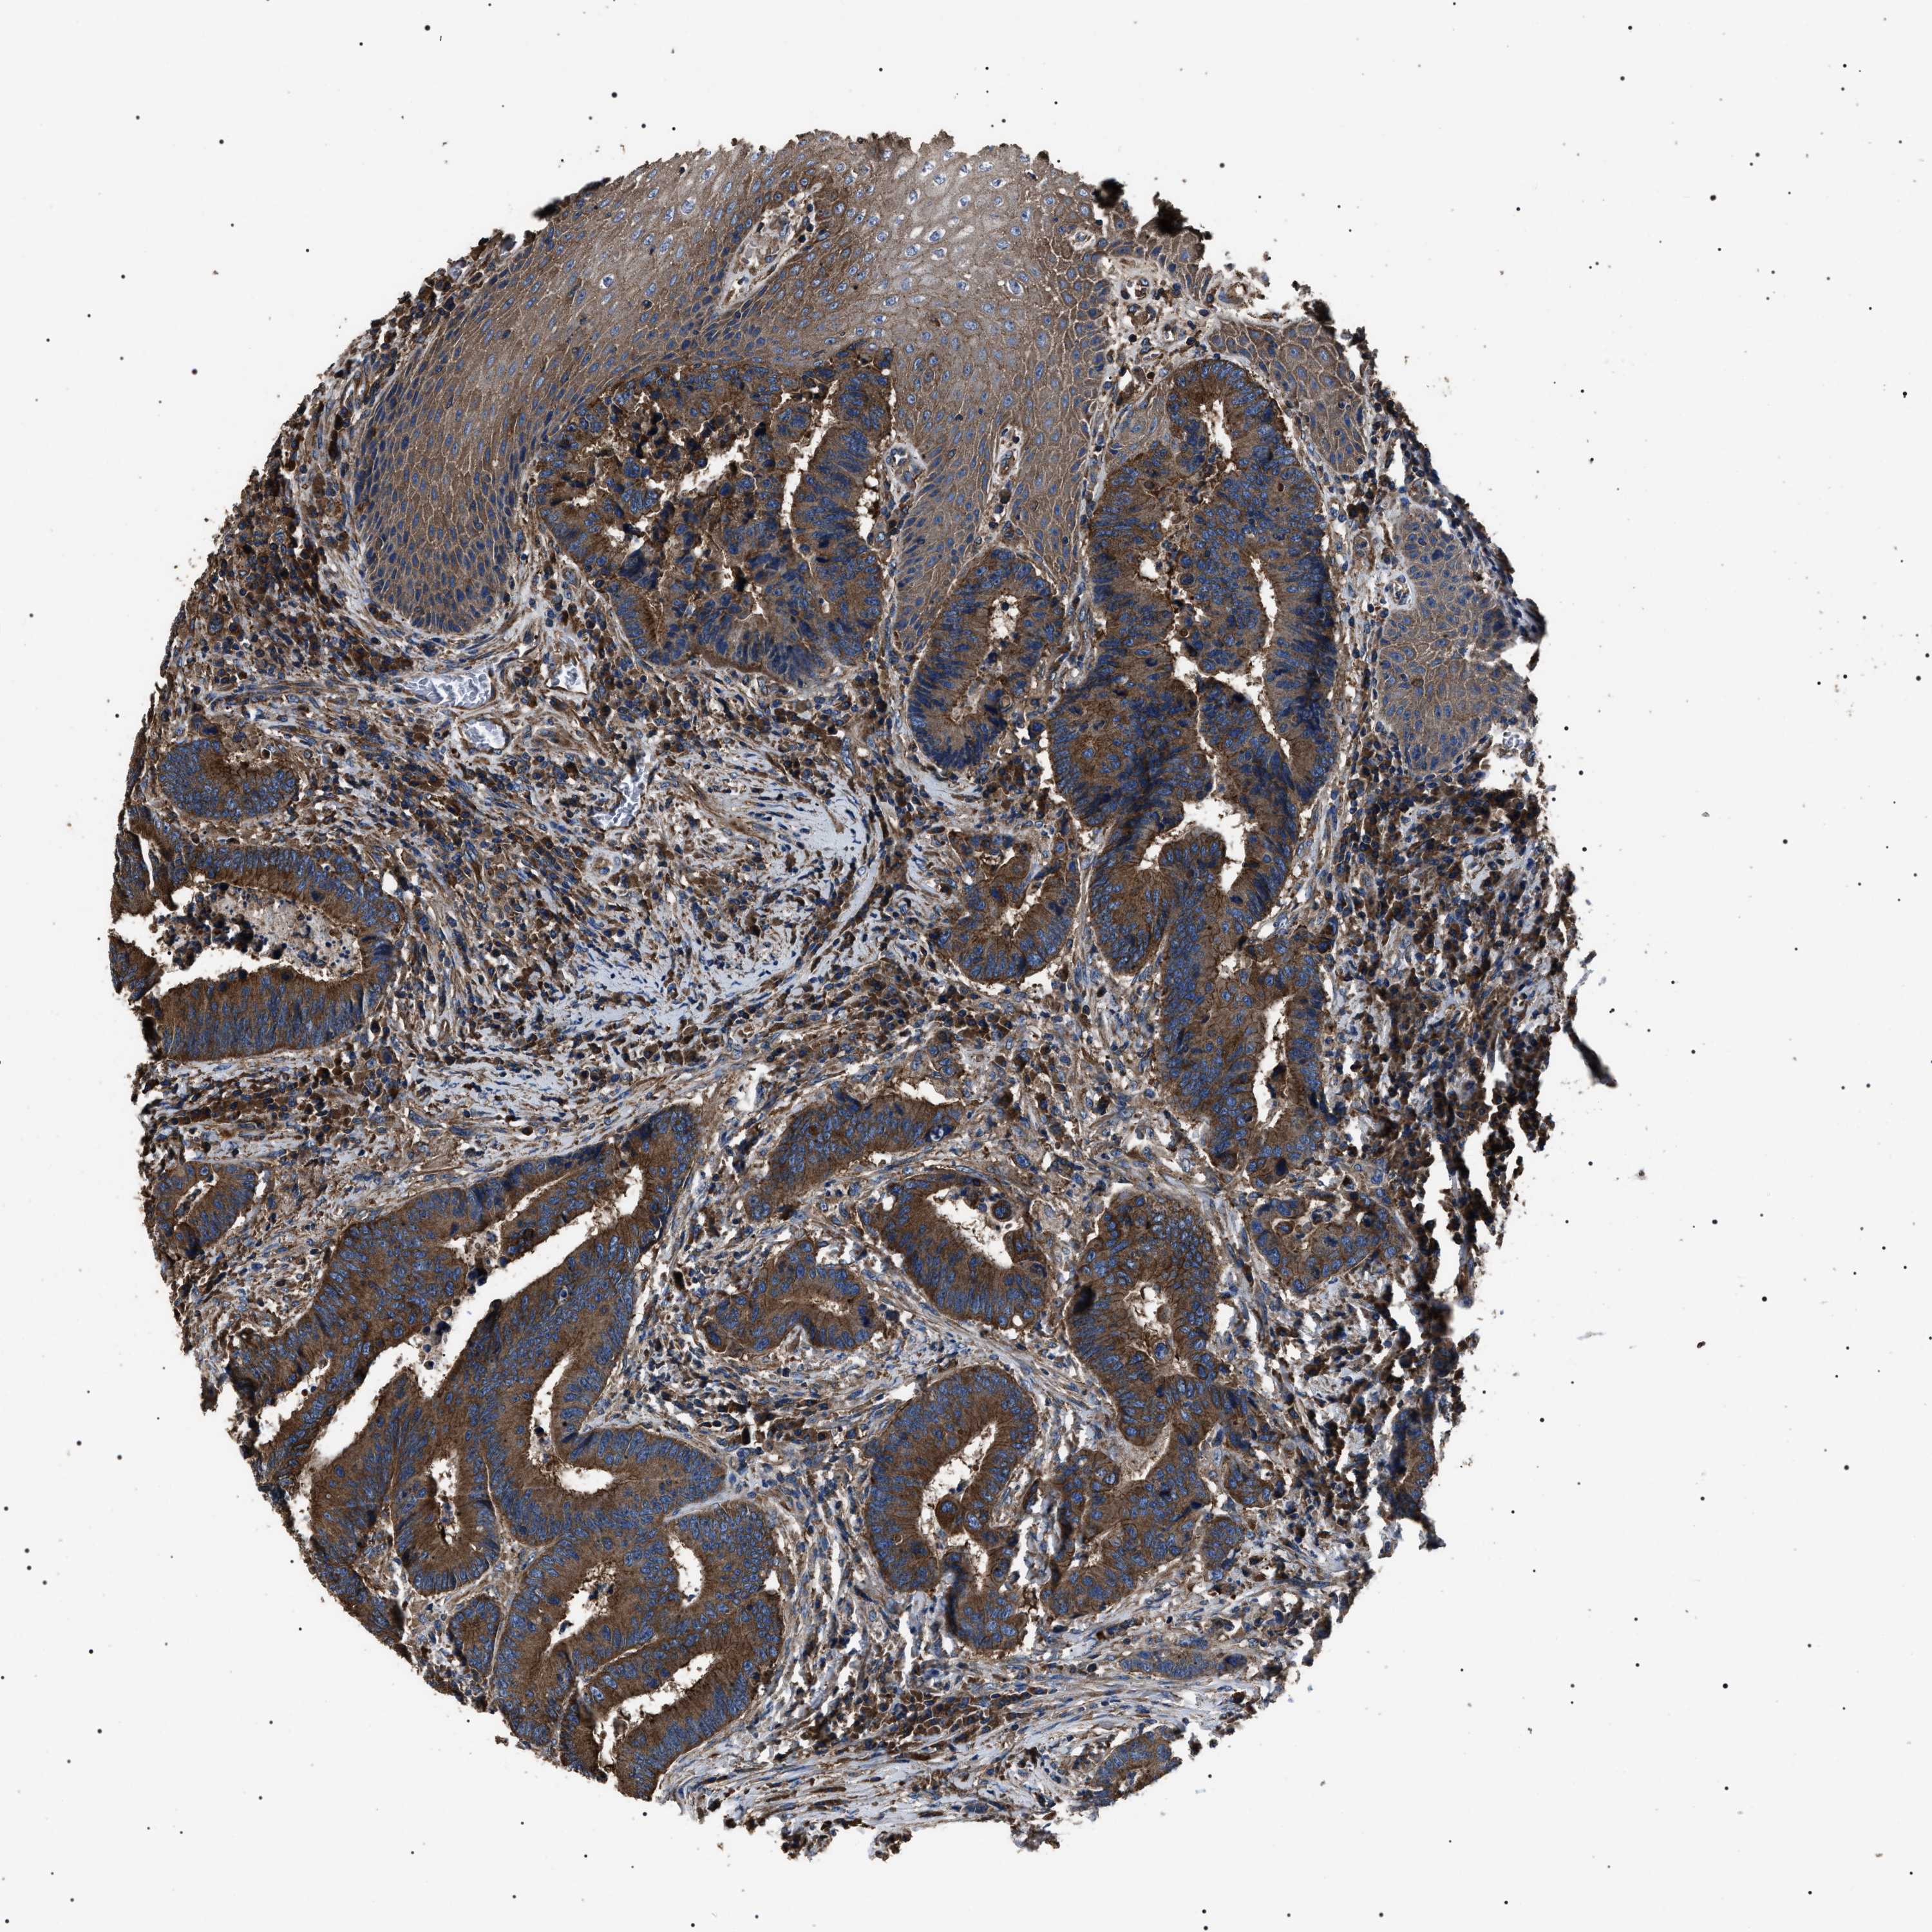

CANCER COLORECTAL CANCER Show tissue menu

Colorectal cancer

Human cancer

Colon adenocarcinoma